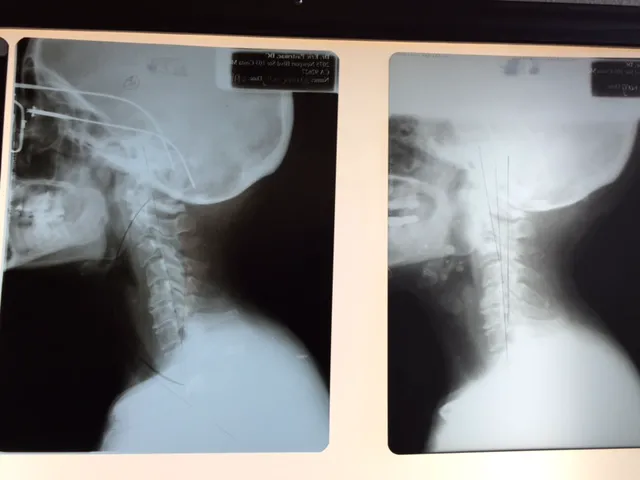

Chiropractic care, at its core, focuses on the diagnosis, treatment, and prevention of mechanical disorders of the musculoskeletal system, particularly the spine, and their impact on nervous system function and overall health. What distinguishes Gonstead Clinics and Dr. Eric Pastrmac is their adherence to the precise and thorough Gonstead System of Chiropractic. This methodical approach involves detailed analysis, including full spine X-rays, static and motion palpation, visualization, and nervoscope readings, to pinpoint the exact location of subluxations (misalignments) in the spine. This precision allows for highly specific and effective adjustments, leading to remarkable patient outcomes. Dr. Pastrmac’s dedication to this meticulous method, combined with his evident skill, has earned him a reputation that extends far beyond Irvine, drawing patients from as far as Los Angeles and beyond.

- Gonstead Spinal Adjustments: The core service, involving detailed analysis using full spine X-rays, nervoscope, palpation, and visualization to identify specific vertebral subluxations. Adjustments are then performed with precision to correct these misalignments, optimizing nervous system function.

- Restoration of Spinal Curvature: Specialized techniques to help restore the natural and healthy curvature of the spine, particularly in the neck (cervical lordosis), which can be crucial for long-term relief from tension and pain.

- Specific Vertebral Correction: Focus on correcting specific misalignments, such as those in the C1, C2, and C4 vertebrae, as highlighted by patient testimonials, which can have profound effects on overall well-being and nerve function.

- Restoration of Neck Curvature and Specific Corrections: A notable highlight is Dr. Pastrmac's success in restoring the natural curvature of the neck and correcting specific, difficult-to-adjust vertebrae like C1, C2, and C4, leading to profound improvements in patient health.

Nov 16, 2021 · susan marozikDr. Pastrmac was able to relieve almost a decade of tension and stress in my neck and back. After my first visit I already noticed a huge difference. He fixed my C1, C2, & C4, and over subsequent visits was also able to restore the curvature in my neck. Years of tension and soreness in my shoulders as well as the tightness in my chest are gone. His work is amazing; I was initially scared to get adjusted, but he put me at ease. I highly recommend him.